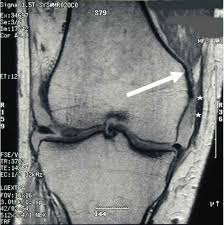

Rapid swelling and possible bruising developing later. (severe sprain or partial tear) high signal is seen medial to the ligament, with high signal or partial disruption of the ligament A ligament sprain is a form of overstretching of the ligament. The knee ligament partially tears. Grade iii tears are also usually treated conservatively unless associated with injuries to the anterior cruciate ligament or posterior cruciate ligament. Free shipping on $35 orders. 3 ways to use video flashcards to engage students and support learning The medial collateral ligament's main function is to prevent the leg from extending too far inward, but it also helps keep the knee stable and allows it to rotate.

Medial collateral ligament (mcl) injuries are graded into three groups on mri, much in the same way as many other ligaments:.

Mild sprain with ligaments stretched but not torn. Injuries to the medial collateral ligament most often happen when the knee is hit directly on its outer side. Grade i is sprained, grade ii is a partial tear, grade iii is a complete tear of the ligament. 3 online classroom games to energize your class; A grade 1 (minor) mcl tear can take from a few days to a week and a half to heal enough for a return to normal activities, including sports. Case discussion typical findings of a grade 2 medial collateral ligament (mcl) injury with associated posteromedial corner injury. A medial collateral knee ligament sprain or mcl sprain is a tear of the ligament on the inside of the knee. Knee sprains and meniscal injuries.

Medial collateral ligament (mcl) injuries. Grade 2 mcl sprain some of the ligaments are torn in this grade of injury. Severe sprain with complete tear of ligaments. Although the knee joint may not hurt or swell very much, a mild ligament sprain can increase a repeat injury risk. (severe sprain or partial tear) high signal is seen medial to the ligament, with high signal or partial disruption of the ligament A medial collateral knee ligament sprain or mcl sprain is a tear of the ligament on the inside of the knee. Crutches and restricted weight bearing This usually causes some instability in your knee joint. Treatment is usually bracing unless there is gross varus instability in which case repair or reconstruction is performed. Medial collateral ligament (mcl) injuries are graded into three groups on mri, much in the same way as many other ligaments:. Hold for about 6 seconds, then lower slowly. 3 online classroom games to energize your class; Knee ligament sprains are graded in severity from one to three: